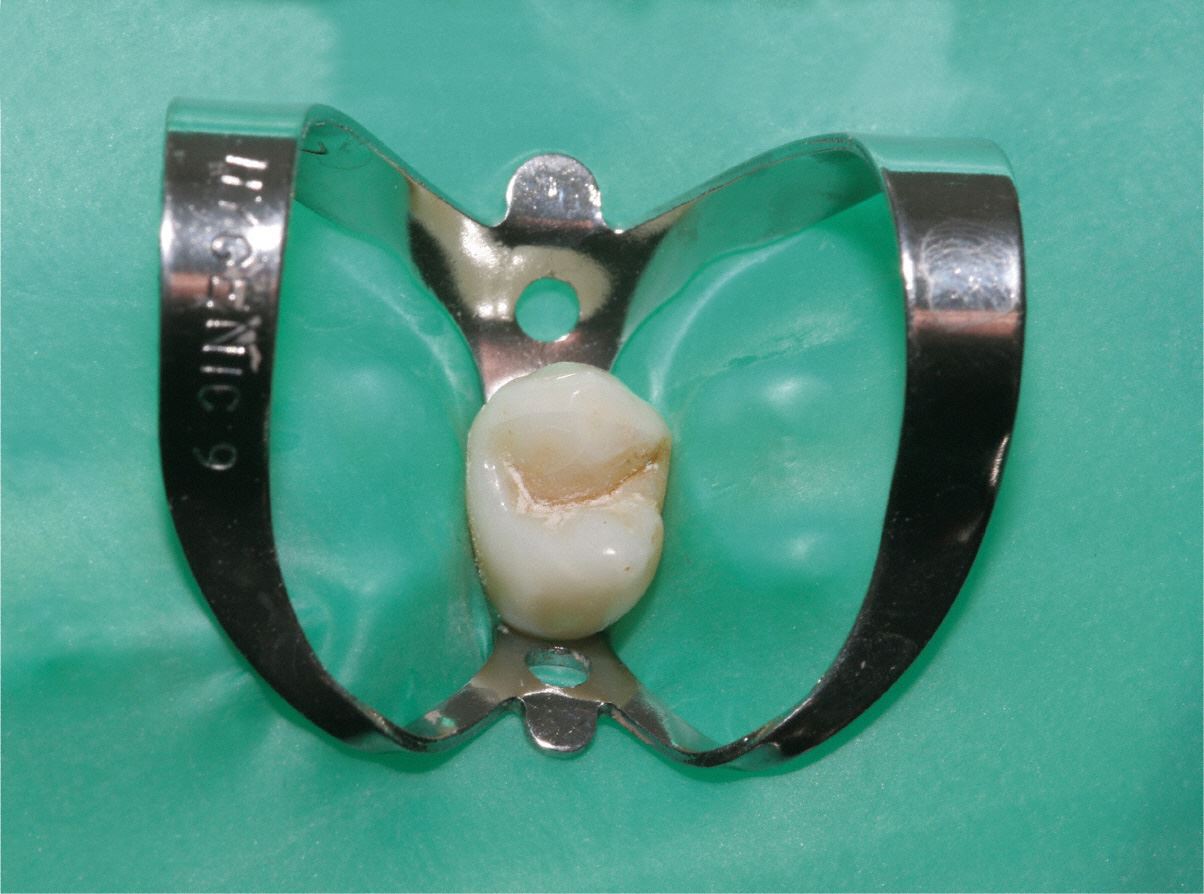

Kofferdam

Für eine effiziente Wurzelbehandlung müssen Bakterien restlos aus dem Wurzelkanal beseitigt werden.

Dafür benutzt man einen speziellen Spanngummi, genannt "Kofferdam", der sowohl den Zahn isoliert, als auch das Eindringen von Bakterien aus der Mundhöhle in den Zahn verhindert. Gleichzeitig wird vermieden, dass der Patient kleine Instrumente oder Materialien verschluckt.

Aufsicht auf freigelegte Kanaleingänge mit Hilfe eines Dentalmikroskops bei geringer Vergrößerung